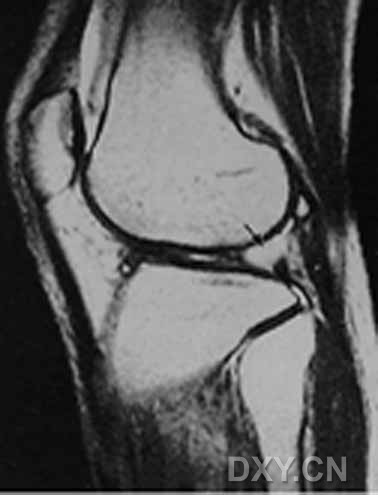

| 0级 外侧半月板表现为均匀低信号,形态规则

| I级 外侧半月板后角见灶性高信号,不与半月板关节面相接触

| Ⅱ级,见黑箭头

| III级 内侧半月板后角内见线形高信号达到半月板的关节面下缘